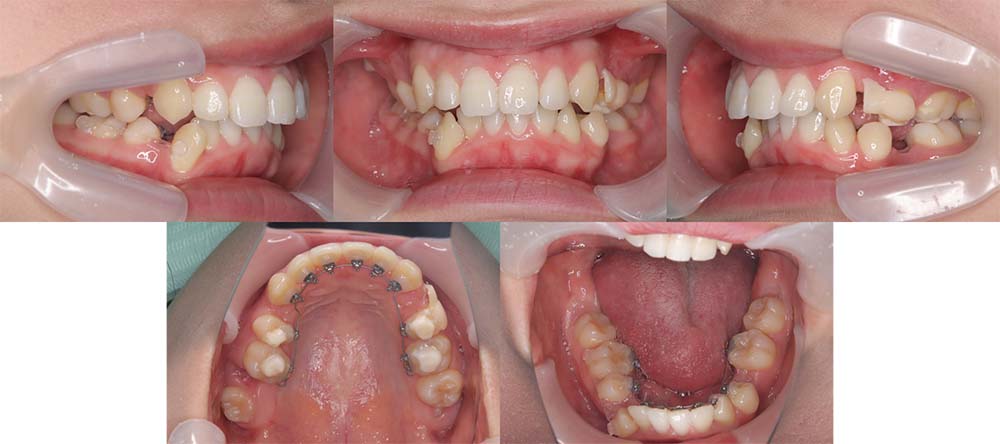

| 症例分類 | 上顎前突、口唇突出 |

| 診断名 | 左下4先天欠損を伴う上下前歯部叢生と骨格性上顎前突 |

| 主訴 | 出っ歯、下の歯がガタガタ、乳歯が1本ある |

| 年齢 | 31歳4ヶ月 |

| 性別 | 女性 |

| 抜歯部位 | 上の左右第一小臼歯と右下第二小臼歯と左下第二乳臼歯(4本) |

| 使用装置 | 上下裏側のワイヤー装置 |

| 治療期間 | 2年9ヶ月 |

| 保定装置 | 固定式保定装置、取り外し式保定装置(8時間) |

| 費用 |

[検査・診断料] ¥49,500 [基本施術料] ¥1,331,000 [調整料] ¥5,500/回 [抜歯] ¥5,500/本 [保定装置] ¥55,000(税込) 抜歯や虫歯治療は他院にて費用が別途かかります。(抜歯¥4,000〜10,000/本)

左下の永久歯が先天欠損で子供の歯が残っていて、その歯が抜けそうになったこともあり、矯正治療を考えて来院されました。

上下叢生と口唇閉鎖不全のため上下の抜歯をして治療をしました。下顎左側乳歯を抜去して治療をしました。

歯の動きが少しゆっくりだったため、予定より治療期間が伸びてしまいましたが問題なく咬合させることができました。